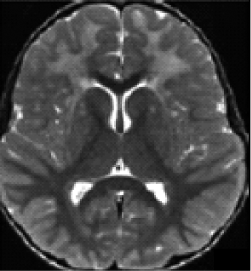

A radiologic diagnosis of Alexander disease is based on the presence of 4 out of 5 MRI features, which are most commonly observed in people with earlier age of onset (ie, infants and young children)1,15,16:

- Frontally predominant white matter changes1

- Periventricular rim abnormalities (eg, high T1-weighted signal and low T2-weighted signal)1

- Abnormalities of the basal ganglia and thalami1

- Brainstem abnormalities1

- Contrast enhancement of 1 or more of the following structures: ventricular lining,

frontal white matter, optic chiasm, basal ganglia, thalamus, fornix, dentate nucleus,

and brainstem1